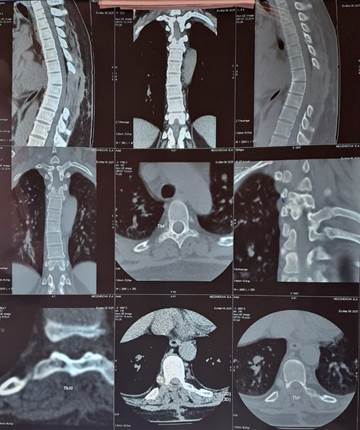

На серии МСКТ грудного отдела позвоночника – состояние после ламинэктомия TH6- TH9, парциальной костотрансверзэктомия в сегментах TH6 - Th7 позвонков с двух сторон, субтотальная резекция объемного образования с декомпрессией спинного мозга; ось позвоночного столба изменена, сколиоз, угол открыт влево, усиление физиологического кифоза; на момент исследования определяются участки кистовидной трансформации с четким склеротическим ободком, частично вскрышегося типа с поражением дуги, поперечного отростка Th4 справа в сочетании поражением с дуго-отросчатого сустава Th4-Th5 справа с признаками артрита; аналогичные изменения в проекции дуги Th10 справа; паравертебрально на уровне тела Th9 справа определяется мягкотканый тофус размерами до 9х10,6 мм; обращает внимание значительный неравномерный субхондральный склероз замыкательных пластин, в сочетании со значительным неравномерным гиперостозом по периметру смежных замыкательных пластин; межпозвонковые диски умеренно равномерно уплощены, без значимых протрузионных изменений, в том числе в сторону СМК и межпозвонковых каналов; патологических изменений в превертебральных мягких тканях не выявлено, неравномерное умеренное уплотнение в зоне оперативного доступа (Рис.4). В последнее время в литературе стали чаще встречаться описания поражения позвоночника вследствие роста тофусов у больных подагрой, в том числе и в молодом возрасте [6,7,8]. Причины образования тофусов в позвоночном столбе не установлены. Изучается значение таких факторов, как вы сокая гиперурикемия, сниженная почечная функция, дли тельность болезни, возраст, количество атак острого артрита [9].

/Sinenko.files/image014.jpg)

Рисунок 4. Компьютерная томография грудного отдела позвоночника (описание в тексте). Стрелки указывают на мягкотканный тофус размерами до 9х10.6 мм, расположенный паравертебрально на уровне тела Th9 справа